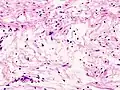

Antoni A area of schwannoma with Verocay bodies (one annotated by circle)_Antoni_B.jpg.webp)